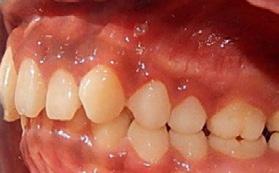

Paciente de 2años y 4 meses, femenino que fue presentada para valoración y consulta, primera dentición y sin caries, presentando hábito pernicioso de protrusión mandibular; normoclusión molar con mordida cruzada anterior (guía canina alterada) (Figura 5). La paciente presentó durante la valoración y consulta una conducta tipo I (- -) según la clasificación de la conducta Frankl y Wright. Mediante una cuidadosa valoración del caso, dada la situación habitual negativa, se diagnosticó como MCA funcional. El plan de tratamiento basado en la posibilidad de realizar un procedimiento práctico y adecuado fue el de realizar solo un ligero y cuidadoso desgaste de los puntos de contacto en la cúspide canina y distal de

Dentista y Paciente 28 Investigación clínica

.5 mm. En la cita subsecuente se observó el objetivo buscado mediante el asentamiento más ideal de la guía canina. La madre Figura 4. A) 72 horas posterior a la colocación. B) Primera activación. C) Segunda activación. D) Avance, tercera cita.

Figura 5. A) Posición de los caninos inferiores alterando la guía. B) Guía canina liberada tras el ajuste oclusal en ambas cúspides caninas inferiores. C) Protrución del labio. D) Retrución de labio una semana después.

reportó la eliminación gradual de la parafunción.